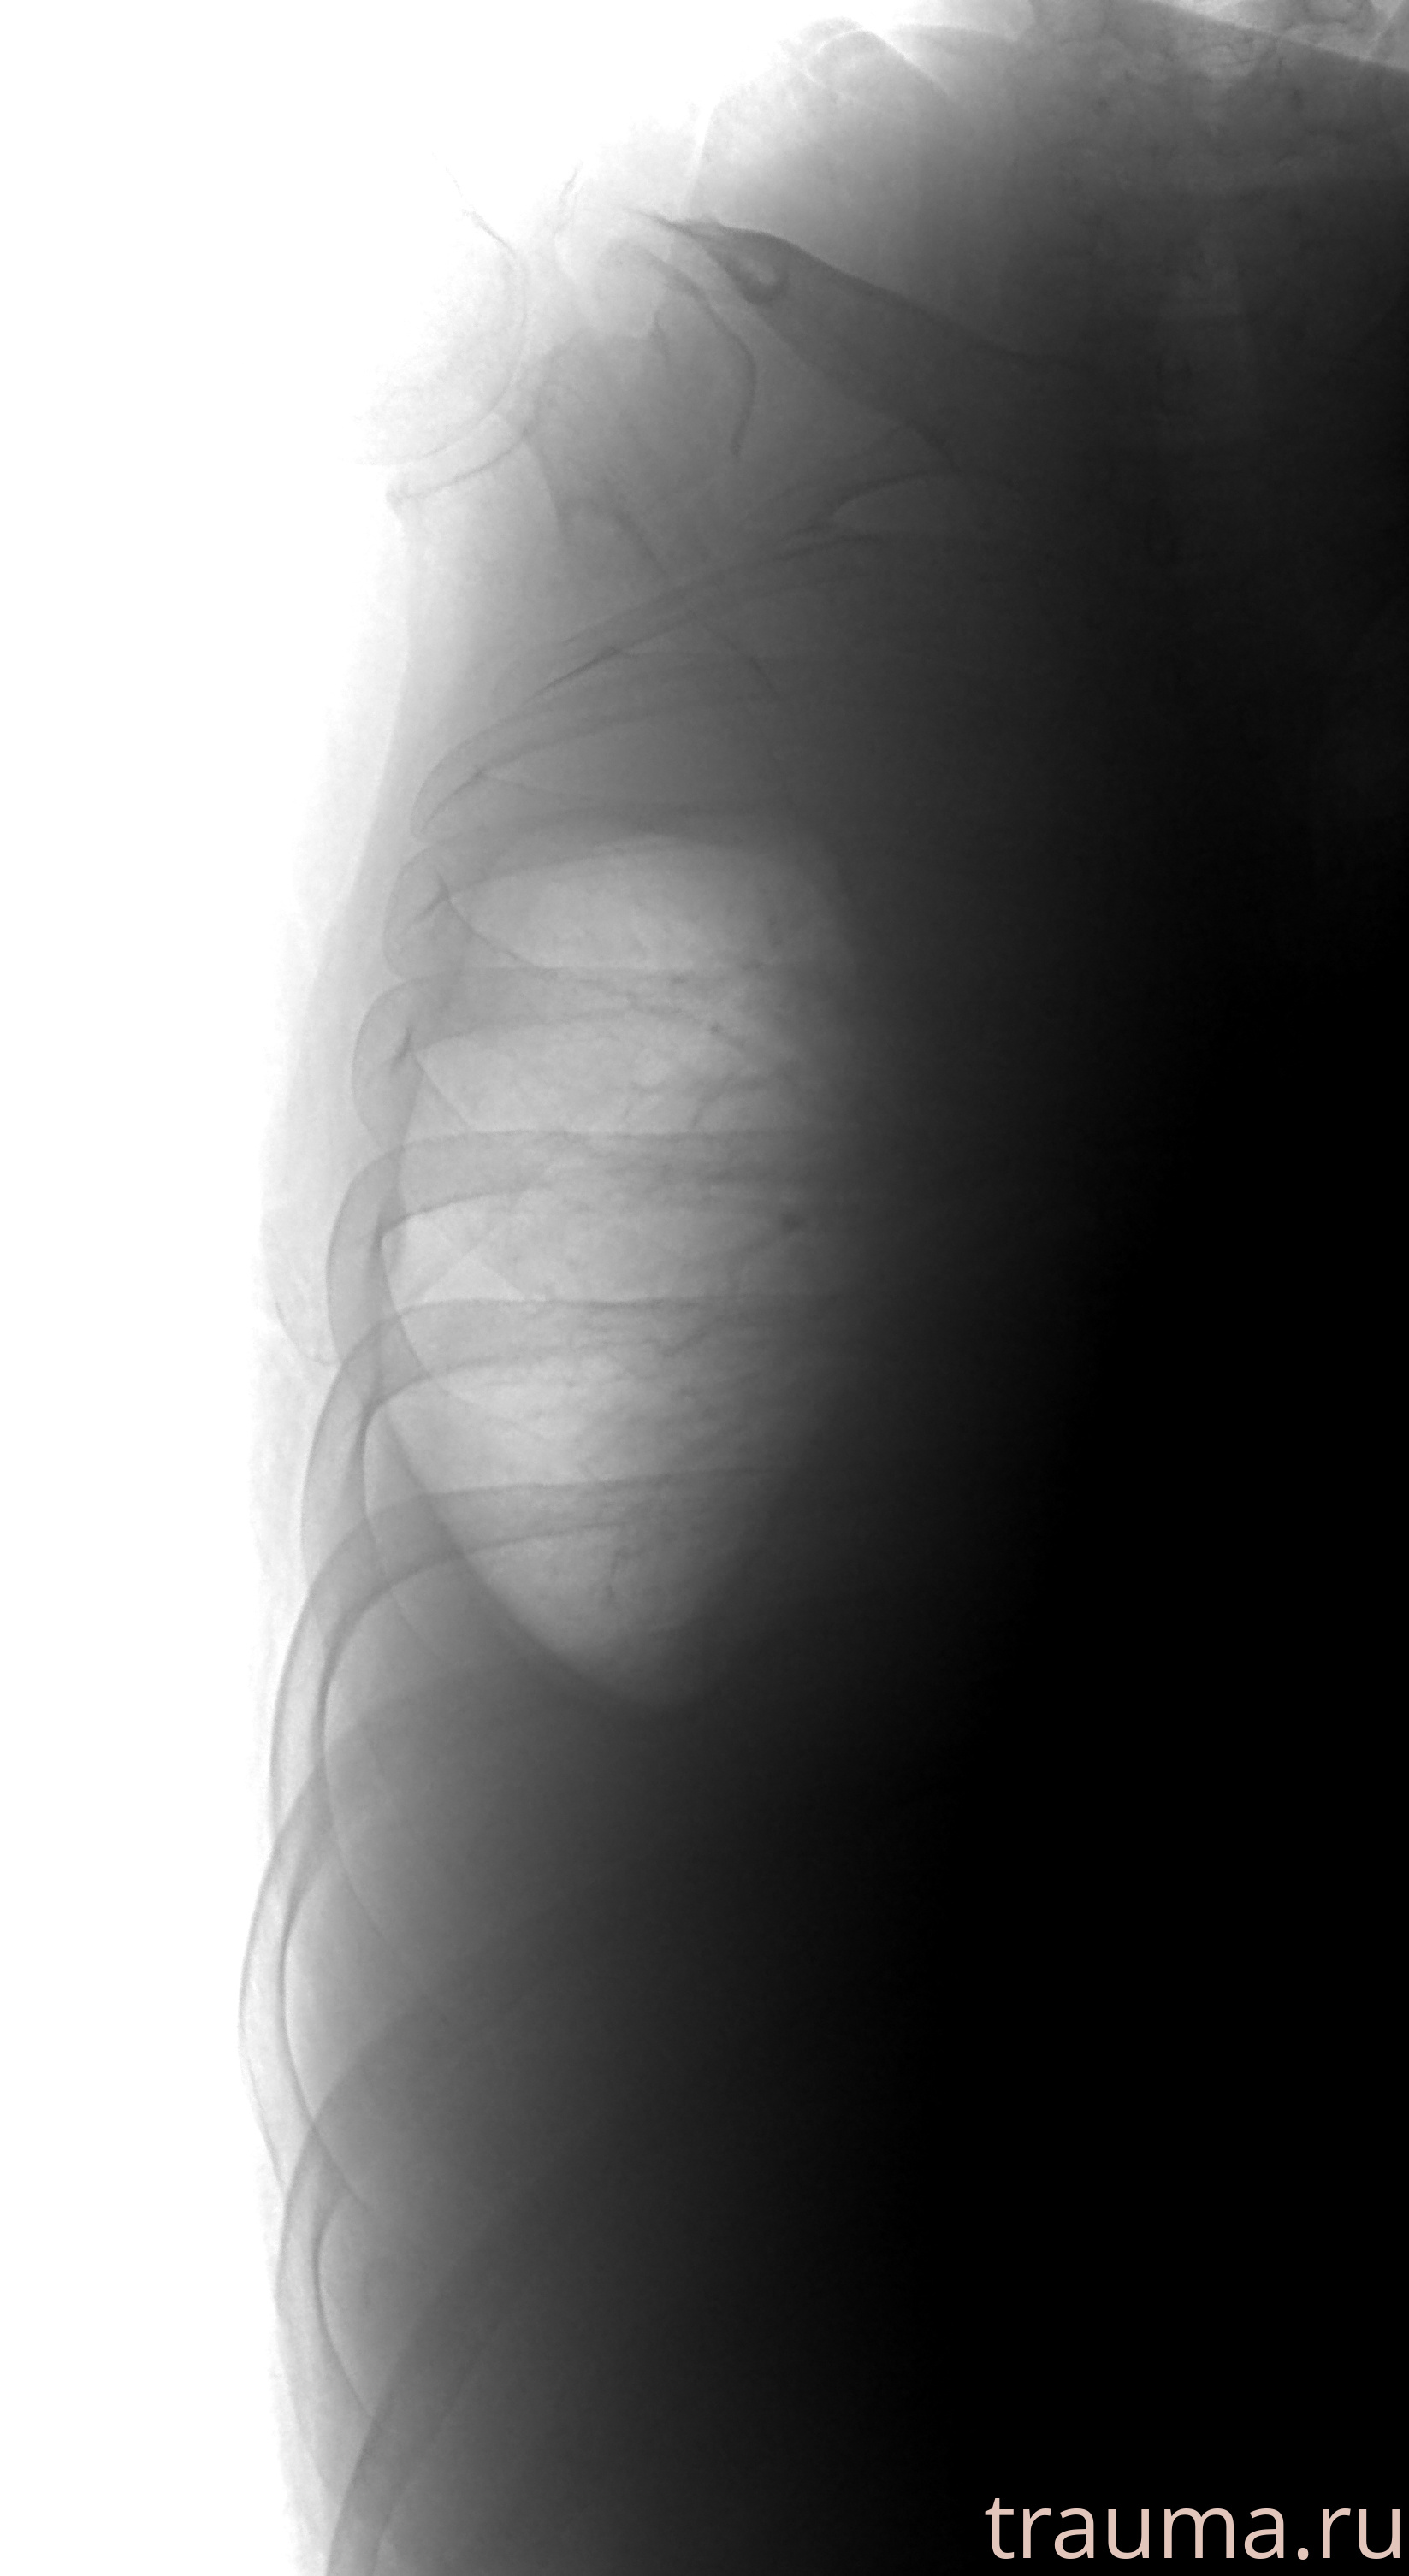

Рентген на дому: по вашему адресу приезжает врач-рентгенолог, травматолог-ортопед с мобильным рентгеновским аппаратом, проводит диагностику травмы или заболевания, делает необходимые рентгенограммы, дает рекомендации по дальнейшему лечению. Получить качественные снимки в домашних условиях возможно благодаря уникальной методике, разработанной МосРентген Центром для института  Склифосовского